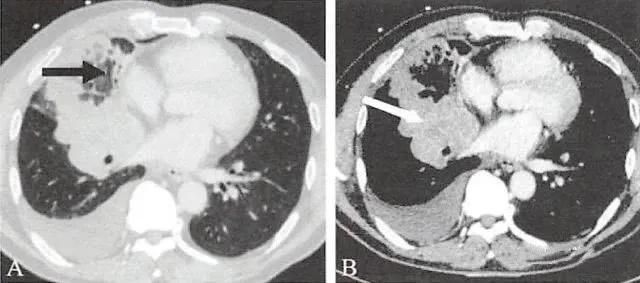

(2)周围型,肿瘤发生在段支气管以下,以腺癌较为多见。

CT易显示肿瘤内的空洞及钙化,空洞多不规则,壁厚薄不均匀,可见壁结节;钙化多为斑片状或结节状。

(3)弥漫型,肿瘤发生在细支气管或肺泡,弥漫分布于两肺。

两肺多发小结节或粟粒状结节,以中下肺为著,常伴有单侧或双侧的胸腔积液。结节大小不等,但每个结节的形态学表现与孤立性周围型肺癌具有相同的特征。